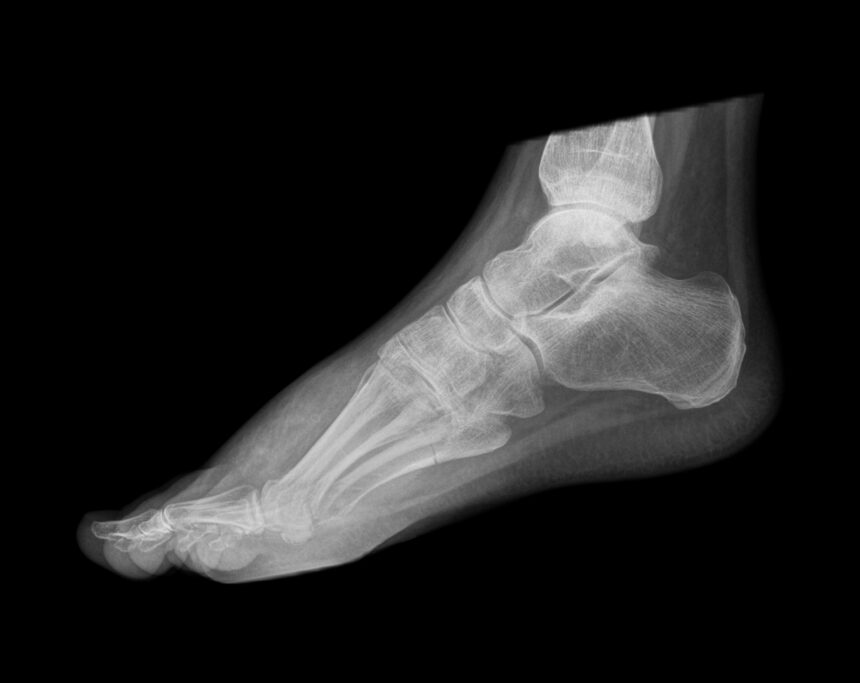

The medical term for a bone spur is an osteophyte, and health professionals encounter them routinely on imaging scans. Most are discovered incidentally, meaning a person never knew they had one until an X-ray was taken for an unrelated reason.

Osteoarthritis is the most common driver of bone spur formation. Repetitive physical activity plays a role as well. Runners, dancers and others who subject their feet to constant hard-surface impact frequently develop heel spurs as the body attempts to reinforce the area. Poorly fitting footwear, excess body weight and nutritional deficiencies that weaken bones can also accelerate the process by placing additional mechanical stress on vulnerable joints.